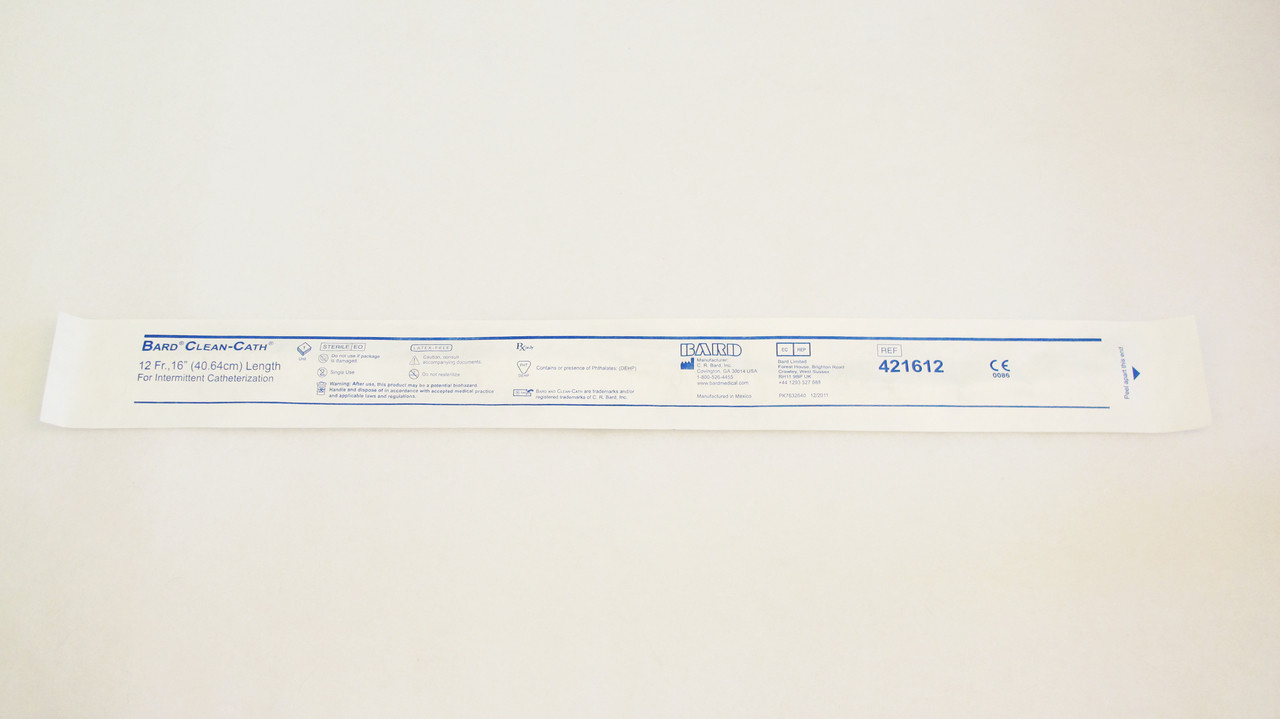

Bard Clean-Cath Vinyl Unisex Catheter

Bard Clean-Cath Vinyl Catheter is suitable for patients requiring a rigid catheter. Smooth eyes are for comfort and safety, the spherical tip minimizes discomfort.1 Each / Each

Clean-Cath Vinyl Unisex Catheter - 16" Buyer’s Guide

The Clean-Cath Vinyl Unisex Catheter - 16" is a straightforward and dependable intermittent catheter designed for both men and women who need a clean, sterile solution for bladder management. Ideal for home use or on the go, it combines comfort, safety, and simplicity in a single-use, latex-free format.

Single-Use and Sterile Packaging

Each Clean-Cath catheter is individually packaged in a sterile, ready-to-use format, making it convenient and hygienic for use at home, work, or while traveling. The tear-open packaging is designed for easy access—even for users with limited dexterity.